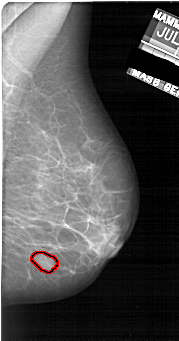

FILE: A_1922_1.RIGHT_CC.OVERLAY

TOTAL_ABNORMALITIES 1

ABNORMALITY 1

LESION_TYPE MASS SHAPE OVAL MARGINS OBSCURED

ASSESSMENT 3

SUBTLETY 4

PATHOLOGY BENIGN

TOTAL_OUTLINES 1

BOUNDARY